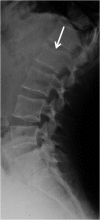

Emergency and trauma care produces a "perfect storm" for radiological errors: uncooperative patients, inadequate histories, time-critical decisions, concurrent tasks and often junior personnel working after hours in busy emergency departments. The main cause of diagnostic errors in the emergency department is the failure to correctly interpret radiographs, and the majority of diagnoses missed on radiographs are fractures. Missed diagnoses potentially have important consequences for patients, clinicians and radiologists. Radiologists play a pivotal role in the diagnostic assessment of polytrauma patients and of patients with non-traumatic craniothoracoabdominal emergencies, and key elements to reduce errors in the emergency setting are knowledge, experience and the correct application of imaging protocols. This article aims to highlight the definition and classification of errors in radiology, the causes of errors in emergency radiology and the spectrum of diagnostic errors in radiography, ultrasonography and CT in the emergency setting.